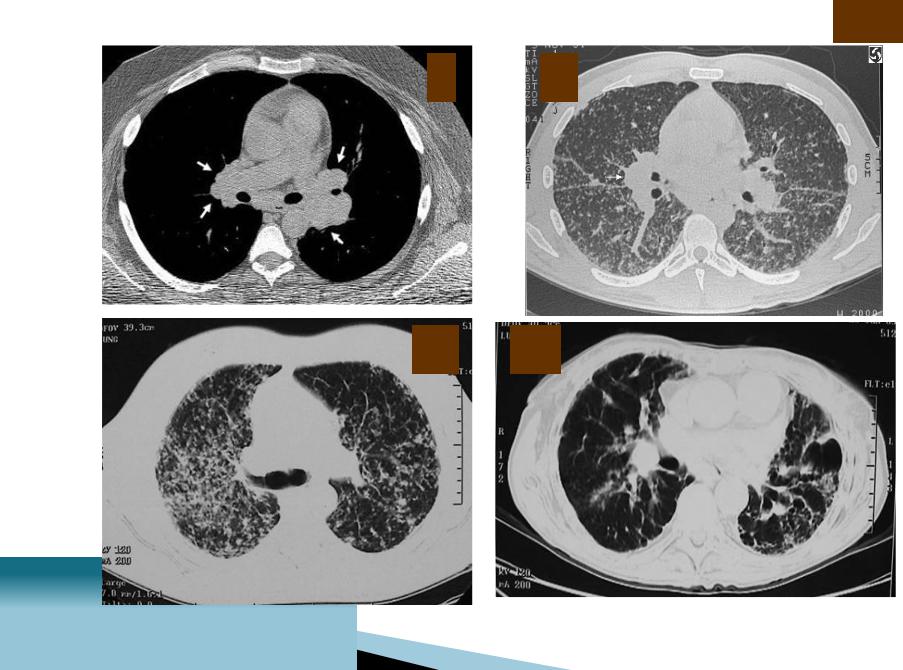

РКТ

I II

III IV